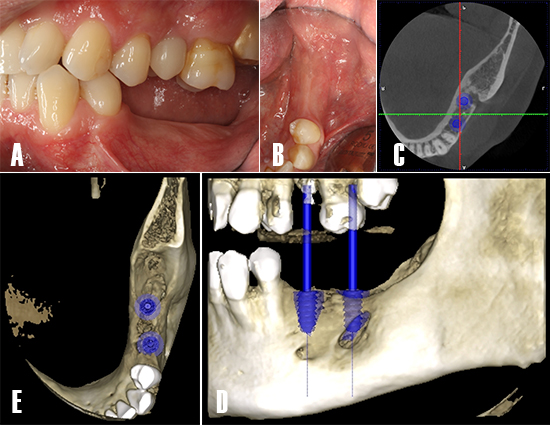

Se planificó la colocación de dos implantes mediante TCHC. Tras la evaluación tridimensional se observó un defecto óseo residual en distal del implante planificado en posición 3.7 (Fig. 11).

Figura 11. Planificación de implantes. Evaluación intraoral de la zona tratada. A) Se evalúa las necesidades protésicas y calidad de los tejidos blandos. B) En un vista oclusal, se observa los tejidos blandos saludables y presencia de mucosa queratinizada. C) Se realiza una TCHC y se planifica la colocación de dos implantes dentales en posición 3.5 y 3.7.

Dos implantes de 4.7 mm de diámetro y 11 mm de longitud fueron instalados (Phibo TSA®, Phibo Dental Solutions, Barcelona, Spain). El defecto residual en distal de 3.7 fue regenerado de forma simultánea con ß-fosfato tricálcico (KeraOs®, Keramat, A Coruña, Spain) (Fig. 12).